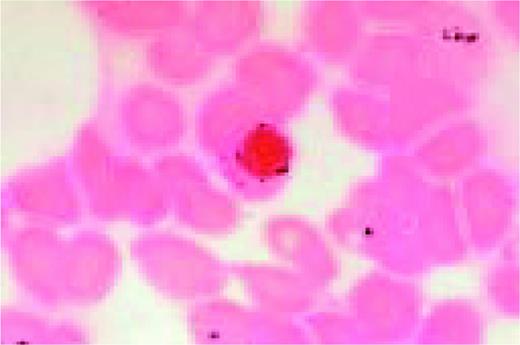

A classic sickle cell is seen in this high-oil magnification field.FIG111